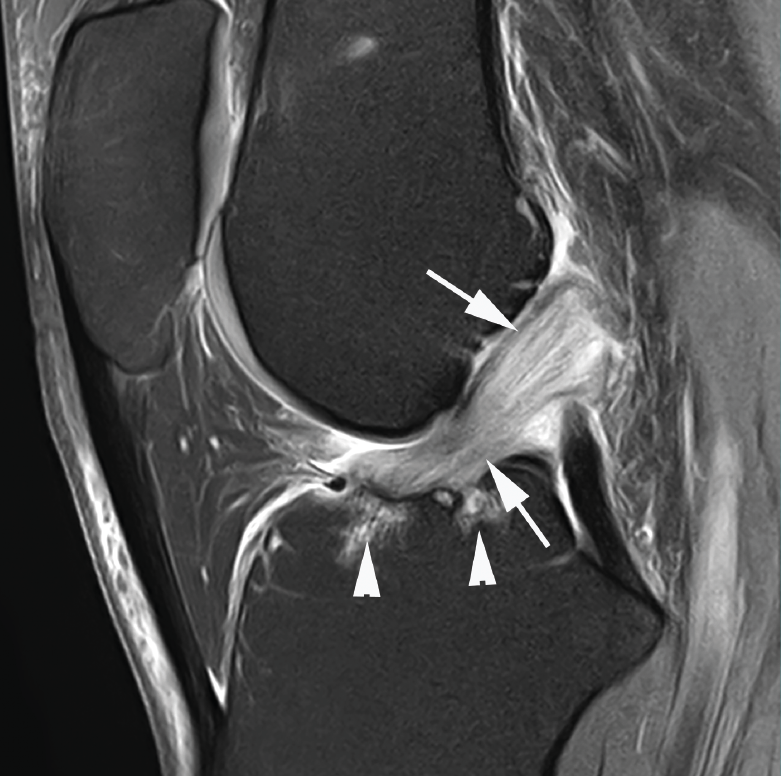

Los hallazgos de RM en las roturas parciales del LCA consisten en un aumento de la señal intrasustancial, defectos focales, distorsión y atenuación de fibras o una orientación anormal del ligamento(1,16)(Figuras 4 y 5). El diagnóstico es más sencillo en fase aguda, por la presencia de signos secundarios con edema y derrame articular. La principal dificultad diagnóstica con RM en la fase aguda consiste en diferenciar roturas parciales de alto grado de completas(1,16).

Figura 4. Rotura parcial del fascículo anteromedial (AM) del ligamento cruzado anterior (LCA) con formación de pequeño ganglión en la escotadura intercondílea. Corte oblicuo coronal (A) y axial (B) de resonancia magnética (RM) potenciados en densidad protónica con supresión grasa que muestran una rotura del fascículo AM (flechas). Fascículo posterolateral normal (cabezas de flecha).